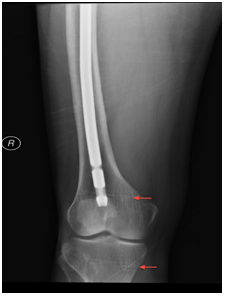

A skeletal survery performed during the hospital stay showed findings consistent with osteomalacia including arrest lines (distal femur and proximal tibia in Figure 3), looser’s zones (shaft of femur in Figure 4), frontal bossing (Figure 5) and multiple endplate compression deformities in the thoraco-lumbar spine (Figure 6).

Figure 3 Distal femur and proximal tibia with arrows showing the arrest lines.